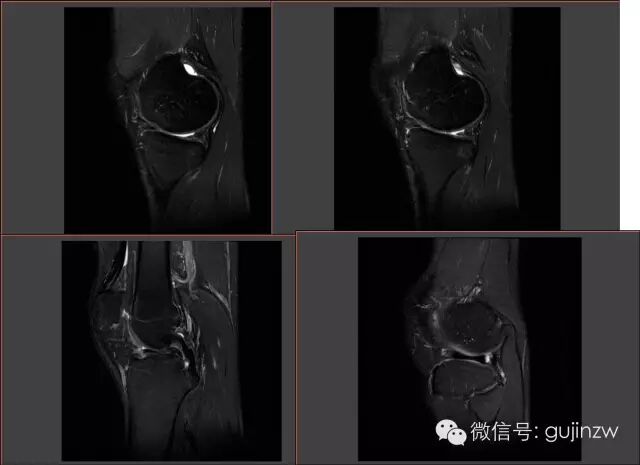

半月板损伤MRI

MRI正常解剖——外侧

内侧

MRI常见征象

• 直接诊断半月板损伤:3度损伤,半月板形态异常,半月板与关节囊分离。

• 征象:蝴蝶结缺失征,多蝴蝶结征,双后叉征。

3度损伤

半月板形体异常、与关节囊分离

蝴蝶结缺失

双后叉征

多蝴蝶结征